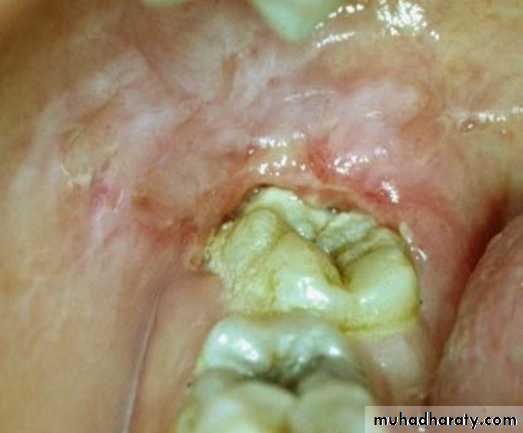

(BRONJ). Exposed necrotic bone is seen at the lingual side of the mandibular right second molar. A lesion with osteolysis and osteosclerosis extends from second molar to first premolar region